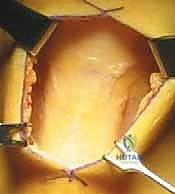

الخطوة الأولى: الفحص بالمنظار الجراحي 4K

يستخدم الدكتور